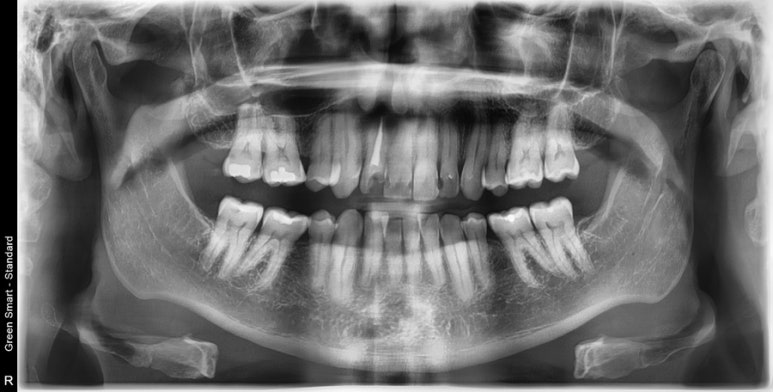

The patient was from the States, a retired veteran who was recommended full mouth extraction and full mouth implant treatment, so-called all on 6 implant treatment.

I was shocked after I see this xray. He had a healthy bone and gum tissue, without any gum disease!

I was really surprised that a dentist recommended full mouth extraction and implant treatment to this kind of patient, especially in States.

I said to the patient, “If I were you, I definitely would save all the natural teeth!”